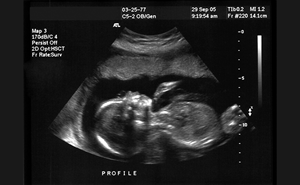

Sound Waves & Sirens: Creating a SonOlympics for EMS Teams Without Prior Ultrasound Training

As a new and enthusiastic member of the ACEP Prehospital, Austere, and Tactical Ultrasound Subcommittee, I’m thrilled to contribute to our mission of expanding the use of ultrasound in prehospital a...